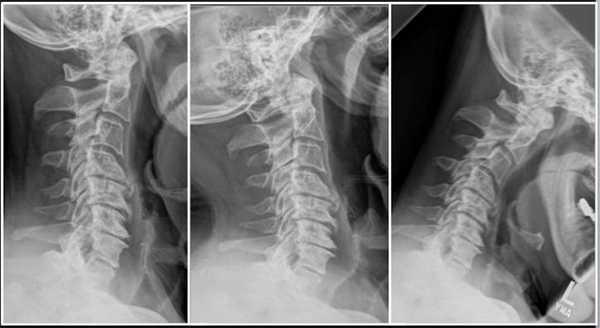

Третье поступление пациента Т. в НИИТО состоялось в августе 2017 г. Жалобы при поступлении: на боли в шейном отделе позвоночника, по наружной поверхности правой руки до 2-3 пальцев, слабость рук, больше слева. Консервативное лечение оказалось неэффективным.

Травматолого-ортопедический статус: сглажен шейный лордоз, симметричное напряжение паравертебральных мышц. Пациент отмечал болезненность при пальпации межостистых промежутков и паравертебральных точек в шейном отделе позвоночника.

МРТ шейного отдела позвоночника: множественные дегенеративные изменения межпозвонковых дисков шейного отдела позвоночника. Дегенеративный стеноз позвоночного канала на уровне С4-С5, С5-С6, С6-С7. Левосторонняя префораминальная протрузия диска С5-С6. Правосторонняя парамедианная протрузия диска С6-С7. Спондилоартроз 2 степени. Фораминальный стеноз С3-С4 С6-С7 с двух сторон, С4-С5 С5-С6 слева.

Пациенту был поставлен диагноз: распространенный остеохондроз шейного, грудного и поясничного отделов позвоночника. Дегенеративный стеноз позвоночного канала на уровне С6-С7 справа. Формирующийся артифициальный костно-металлический блок на уровне Th10-L1 после транспедикулярной фиксации. Формирующийся артифициальный костно-металлический блок на уровне L4-L5, L5-S1 после транспедикулярной фиксации и заднего межтелового спондилодеза. Компрессионно-ишемическая радикулопатия С7 справа. Выраженный болевой синдром.

Была проведена операция: тотальная дискэктомия С5-С6, С6-С7, микрохирургическая декомпрессия спинного мозга и его корешков, вентральный межтеловой спондилодез имплантатом из пористого никелида титана.

Послеоперационный период протекал без осложнений. Корешковая симптоматика купирована. Пациент был выписан на амбулаторное лечение у невролога по месту жительства.